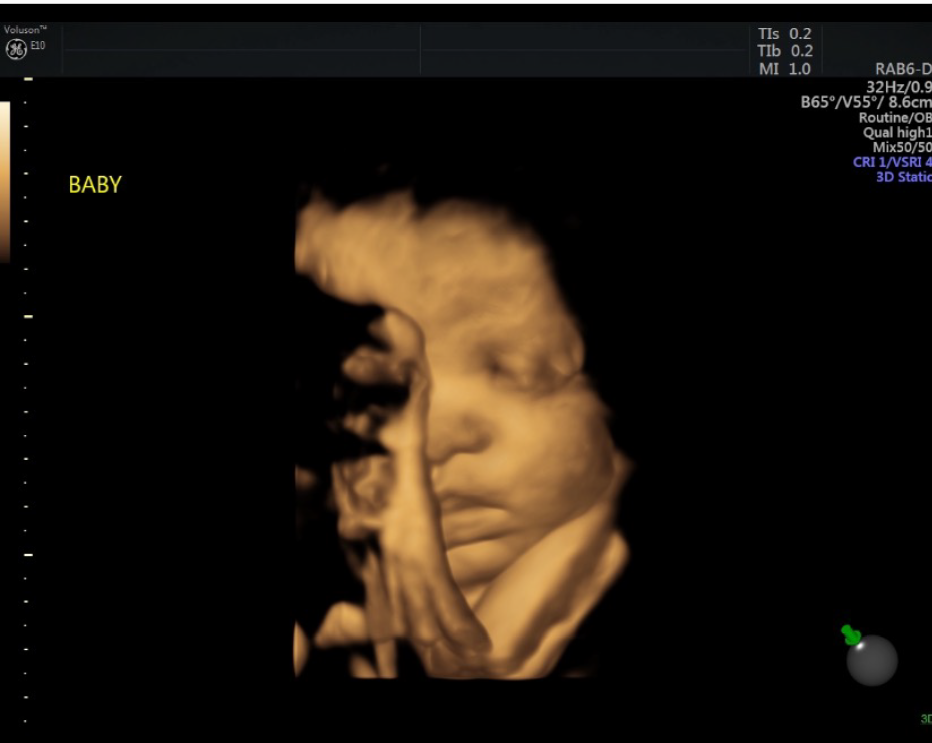

Ashley said several times over the phone that she just wanted to see the baby’s heartbeat, Hale said. They were successful in getting the progesterone started and Ashley came into the pregnancy help medical clinic Monday morning for an ultrasound.

“She brought her mom with her,” Hale told Pregnancy Help News. “Words can't capture the relief shown and then absolute glow on her face as we showed her the baby's heart beating. I'll never forget Ashley's excitement as she grabbed her mom's hand and said, ‘Mom, that's my baby!’”

Ashley gave birth to daughter Thailynn in August 2021.